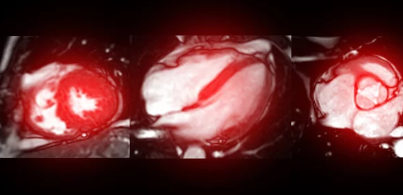

관상동맥 협착증은 심장을 둘러싸고 있는 관상동맥이 좁아져서 혈액 공급이 제대로 이루어지지 않는 상태를 말합니다. 이는 심장에 산소와 영양분을 전달하는 데 중요한 역할을 하므로, 조기에 진단하고 적절히 치료하는 것이 중요합니다. 이번 글에서는 관상동맥 협착증의 치료 방법에 대해 알아보고, 최신 연구와 치료 트렌드를 포함하여 자세히 설명하겠습니다.

관상동맥 협착증은 혈관 내벽에 플라크(지방, 콜레스테롤 등)가 축적되면서 혈관이 좁아지는 질환입니다. 이로 인해 심장으로 가는 혈류량이 줄어들게 되며, 심각할 경우 협심증이나 심근경색과 같은 치명적인 합병증으로 이어질 수 있습니다.

- 스텐트 삽입술(PCI): 좁아진 혈관을 확장시키기 위해 스텐트를 삽입하는 방법입니다. 비교적 간단한 시술로, 회복 시간이 짧아 많이 사용됩니다.

- 관상동맥 우회술(CABG): 심각한 협착이 여러 곳에서 발생했거나 약물 및 스텐트 치료로 해결되지 않을 경우, 우회로를 만들어 혈류를 복원하는 수술입니다.